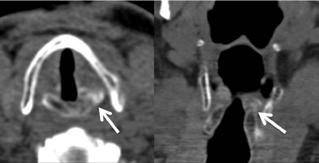

We conducted a retrospective chart review to compare four characteristics—cricoarytenoid joint ankylosis, narrowing, erosion, and density increases—in patients younger and older than 65 years. Our study population was made up of 100 patients, who were divided into two groups on the basis of age. The younger group (<65 yr) comprised 49 patients (27 men and 22 women), and the older group (≥65 yr) was made up of 51 patients (25 men and 26 women). Findings on computed tomography (CT) of the neck were used to determine whether each of the four characteristics was present or absent. Overall, we found only one statistically significant difference between the two groups: ankylosis was significantly more common in the older group (p = 0.036). When we looked further at the side of these anatomic changes, we found that the older group had significantly more right-sided and left-sided ankylosis than did the younger group (p = 0.026 for both), as well as significantly more left-sided narrowing (p = 0.028) (some patients had bilateral involvement). When we analyzed age as a continuous variable, older age was again associated with significantly more ankylosis (p = 0.047) and narrowing (p = 0.011). We conclude that CT can be useful for assessing radiologic changes in the cricoarytenoid joint in elderly patients during the workup of dysphonia and abnormal movement of the vocal folds.

With age, many changes affect the laryngeal structures; among them are the cricoarytenoid joints. These diarthrodial joints are formed by the articular facets of both the cricoid and arytenoid cartilages apposed in a multiaxial form.1 In the elderly—which for the purposes of this study we defined as those aged 65 years and older—the articulation begins eroding and the perichondrium becomes thicker, which affects the precise movement of the arytenoid cartilages over the cricoid cartilage and alters the position of the vocal folds during phonation. These histologic and structural changes result in a change in voice quality.2-4

Among the different laryngeal imaging modalities, computed tomography (CT) is the best for assessing the cricoarytenoid joint. With its rapid image acquisition and low susceptibility to artifact induced by breathing and swallowing, it is considered by many to be the standard diagnostic imaging study for the evaluation of organic voice disorders.5 Modern CT scanners allow for a reconstruction of high-quality images in multiple planes and orientations, and they provide excellent spatial resolution.5